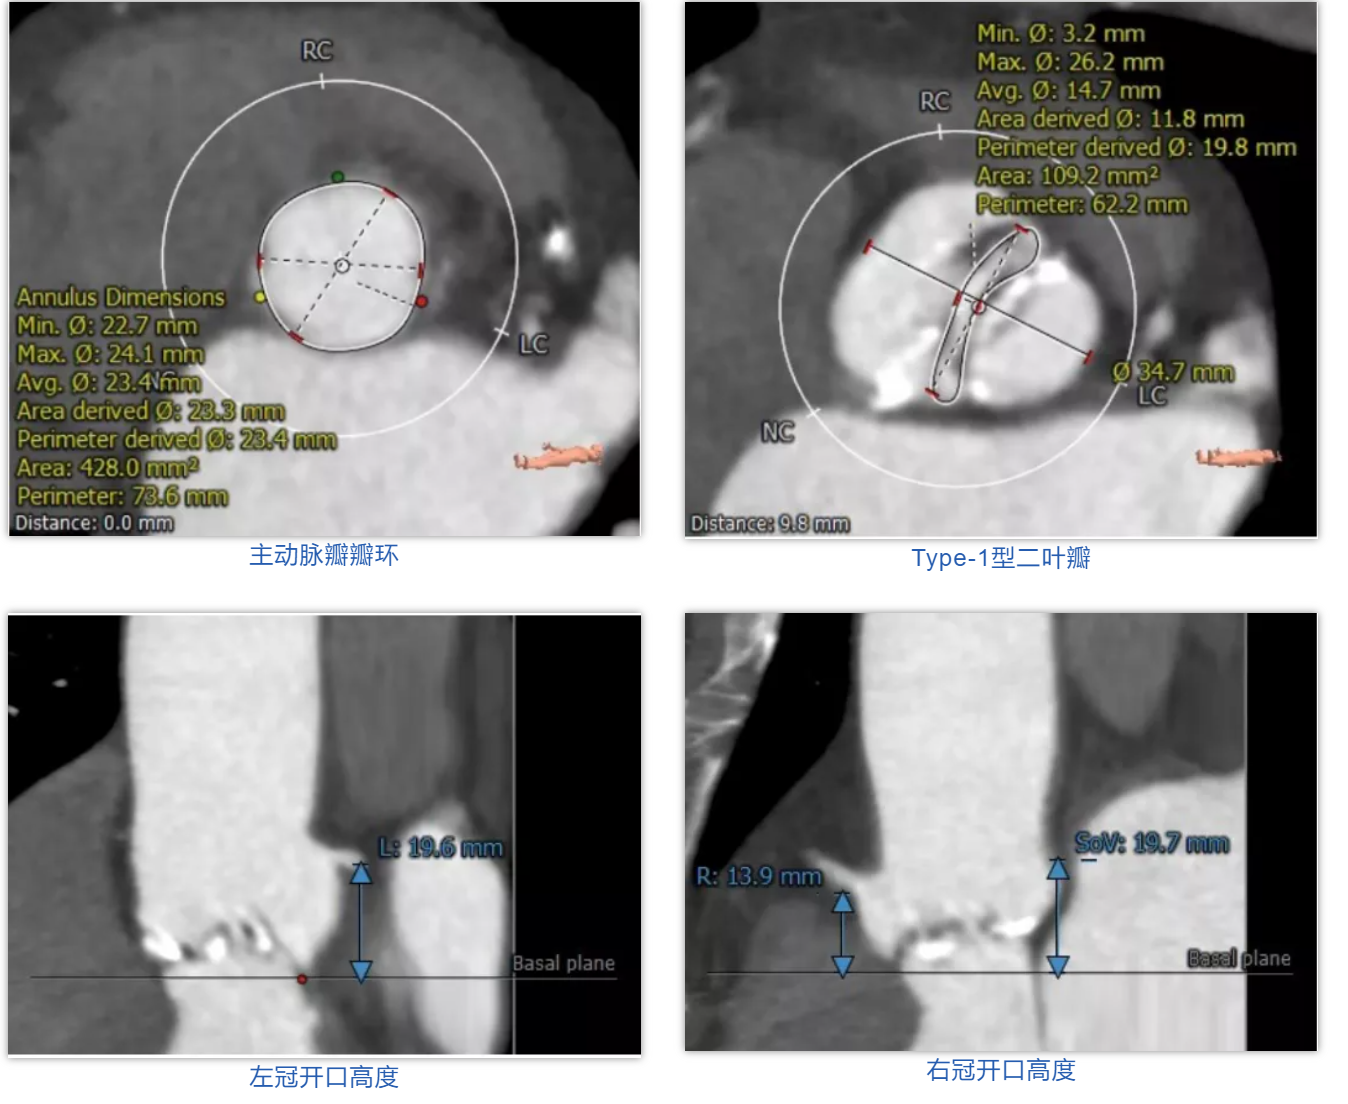

病例2

患者男性,77岁。术前心脏超声提示主动脉瓣钙化,重度狭窄,轻度反流。CT评估结果显示主动脉瓣为Type-1型二叶瓣,瓣叶增厚钙化,瓣环平均直径23.4mm,瓣环面积428.0mm²,面积径23.3mm。左冠脉开口高度19.6mm,右冠脉开口高度13.9mm。术前经详尽影像学重建、评估及病例讨论,测量瓣环直径,评估冠脉梗阻风险后,计划植入23# Renatus介入主动脉瓣。